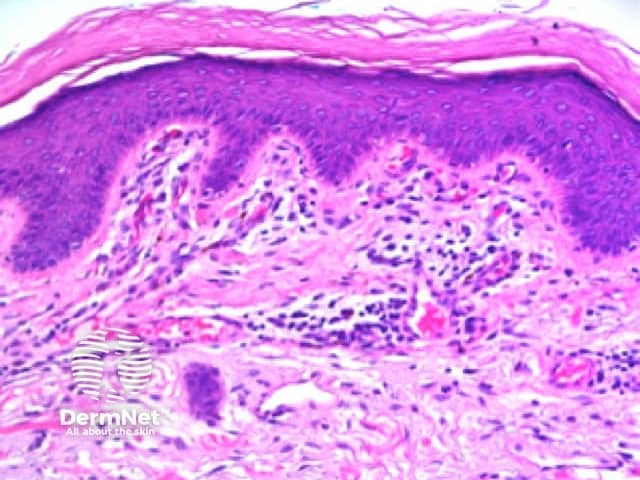

Reticular lines are straight and intersect at regular intervals at right angles. Branched lines are also straight but intersect at irregular intervals and not at right angles. The distinction is not always clear cut and rarely of great importance. These dermatoscopic patterns are seen in lesions in which there is basal epidermal hyperpigmentation and / or a proliferation of pigmented melanocytes preferentially involving the epidermal rete ridges with preservation of the epidermal architecture (Figure 5).

Figure 5